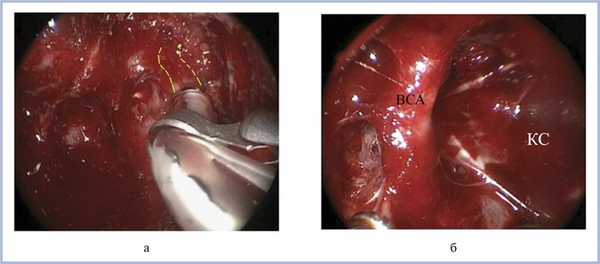

На рис. 4 представлен пример использования устройства для интраоперационной УЗДГ.

Рис. 4. Интраоперационное фото - удаление эндо-супра-латеро (S)селлярной аденомы гипофиза при ЛРТЭД (вид с использованием 30° эндоскопа). а - лоцирование кавернозного сегмента внутренней сонной артерии перед вскрытием ТМО; пунктирной линией обозначена ВСА, расположенная на глубине около 6 мм; б - полость кавернозного синуса (КС) после удаления опухоли; ВСА - кавернозный сегмент внутренней сонной артерии.